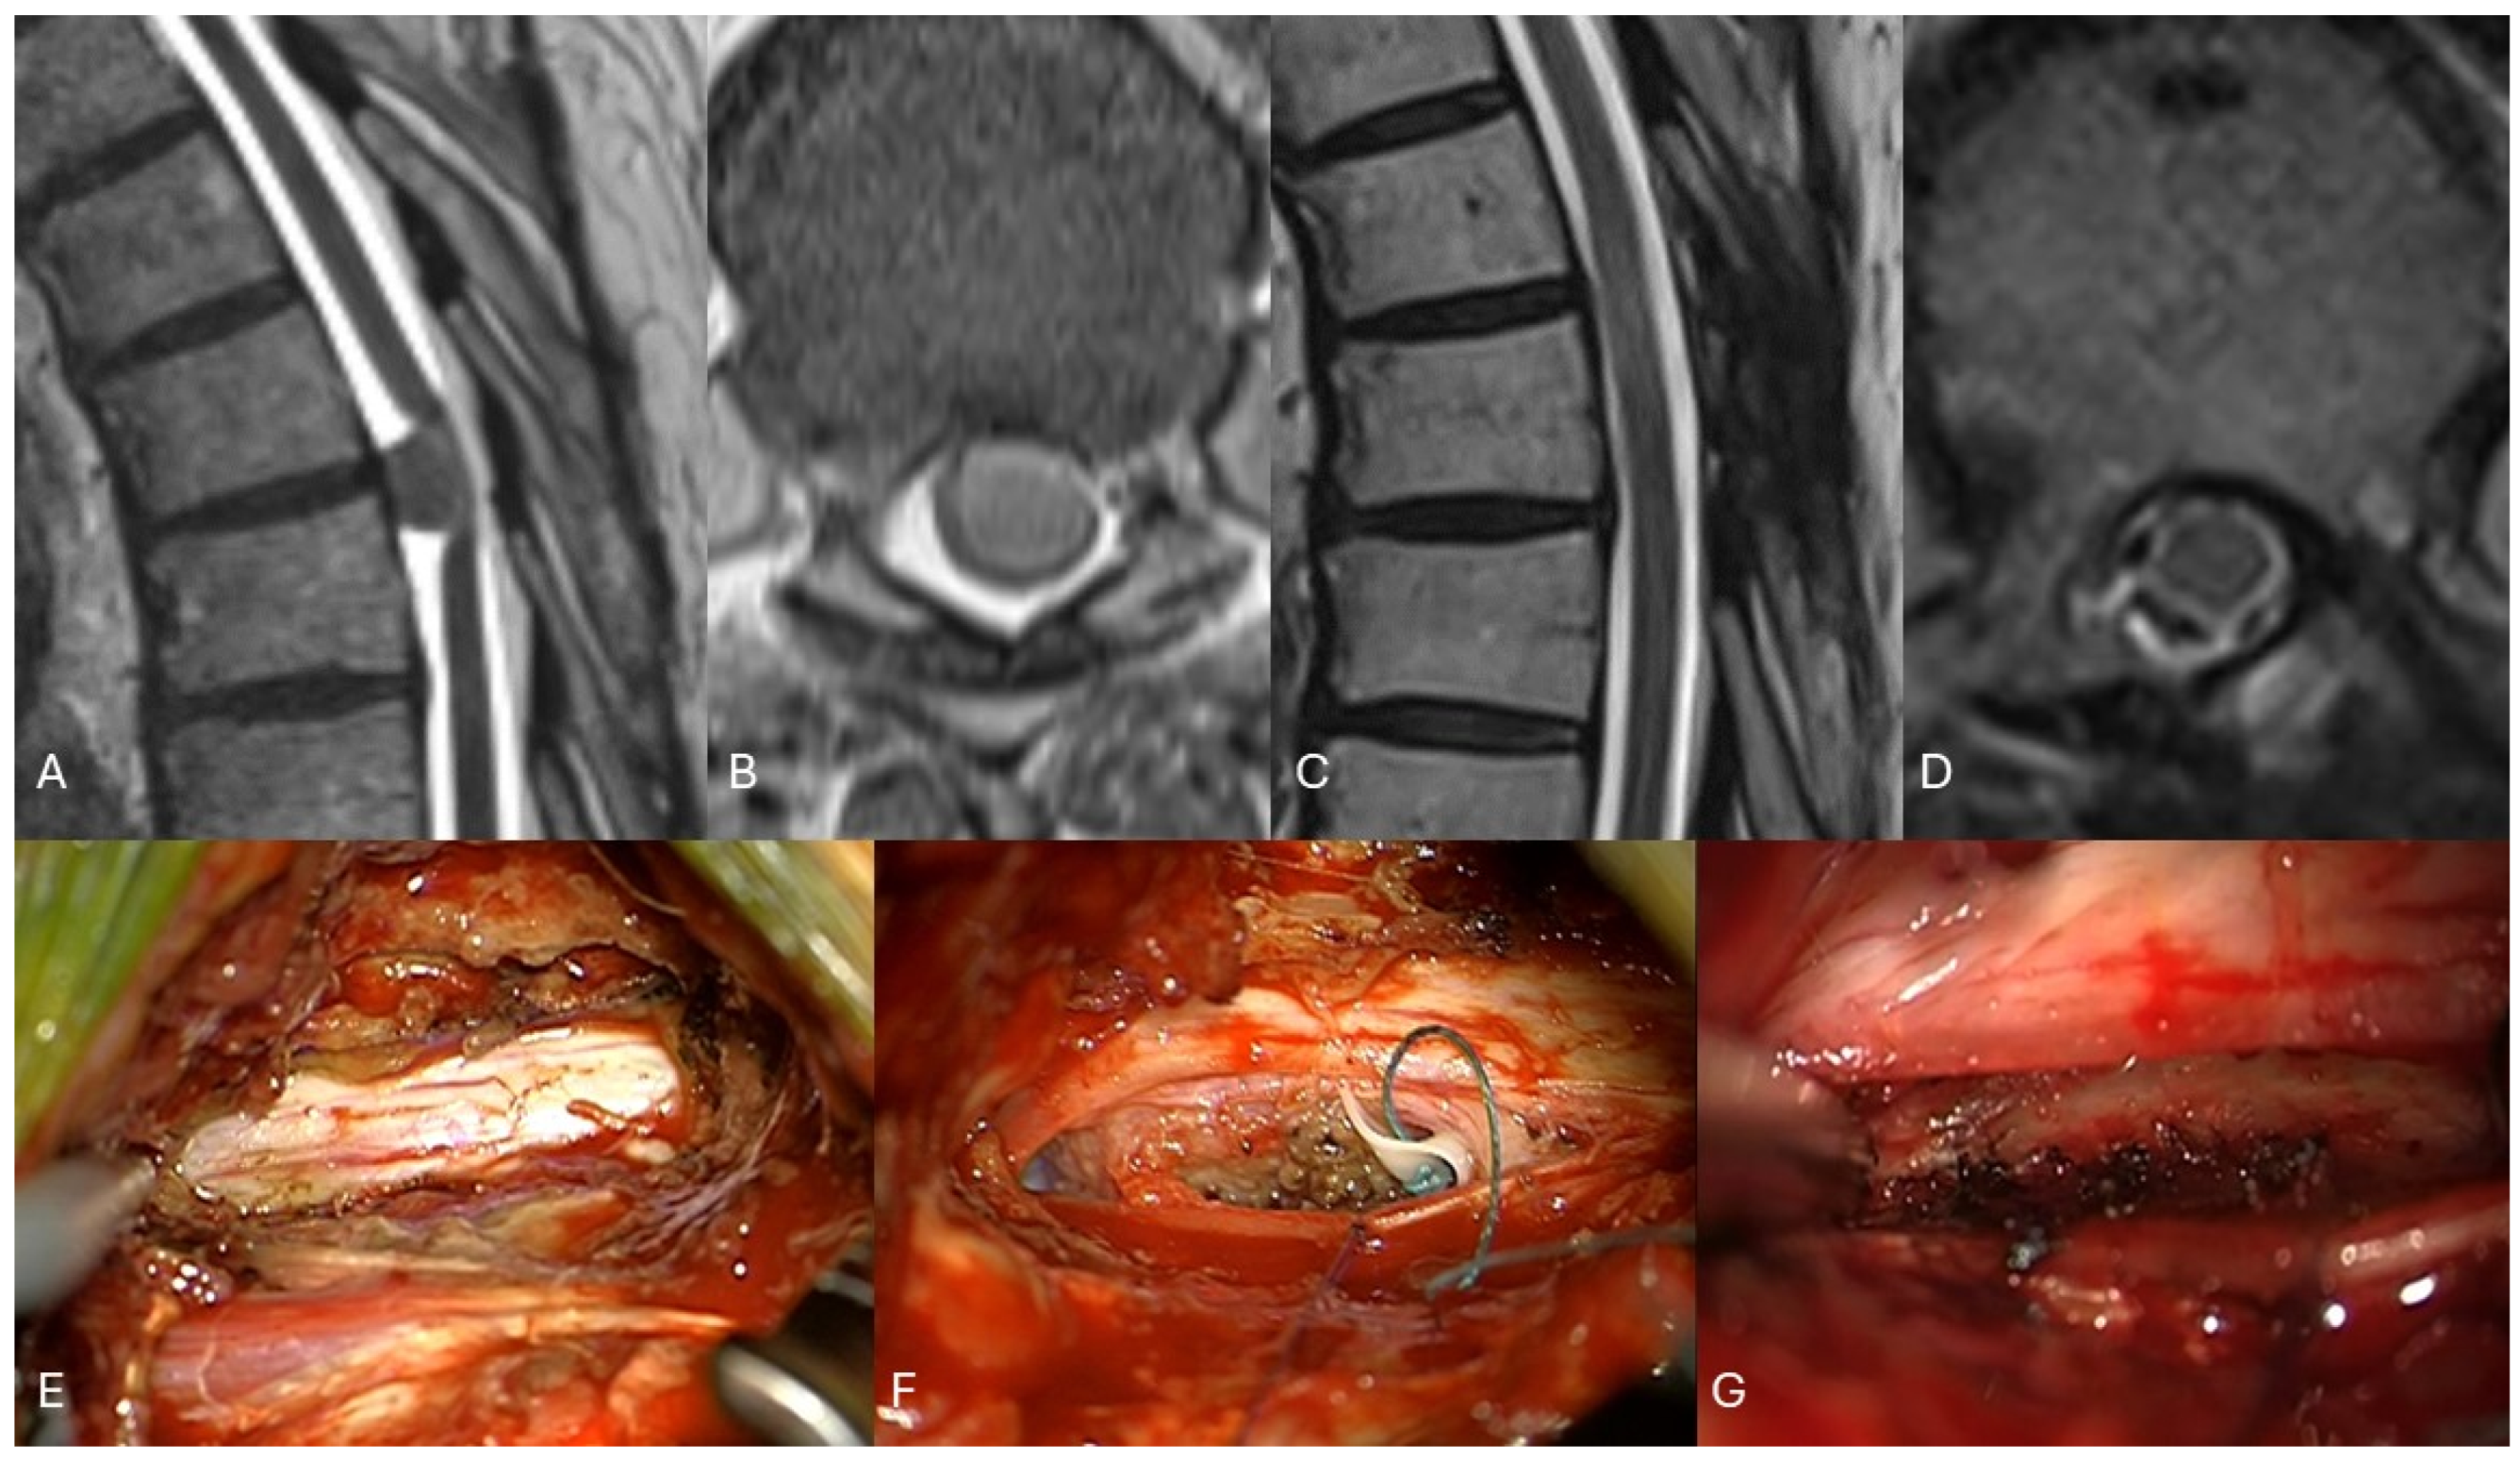

2.2. Surgical Intervention

4.4. Minimal-Invasive Surgery